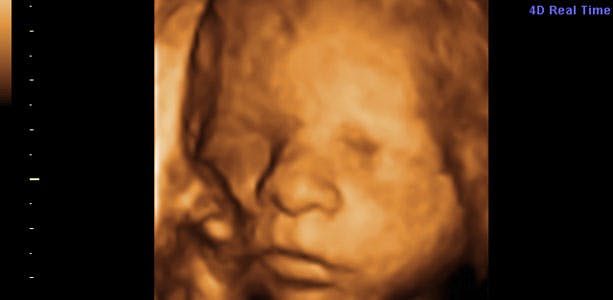

Gravid uge 24: Reagerer på dit humør

Din baby reagerer nu på forskellige sanseindtryk, og af alle lyde foretrækker det din stemme. Lige præcis lyden af din stemme spiller en vigtig rolle for udviklingen af de allerførste bånd mellem dig og dit barn. Barnet hører også omgivelsernes stemmer og kan på denne måde også lære resten af familien at kende. I slutningen af ugen måler barnet cirka 30 centimeter og vejer 700-750 gram. Lårbensknoglen måler cirka 4,1 centimeter og hovedet diameter cirka 5,5 centimeter